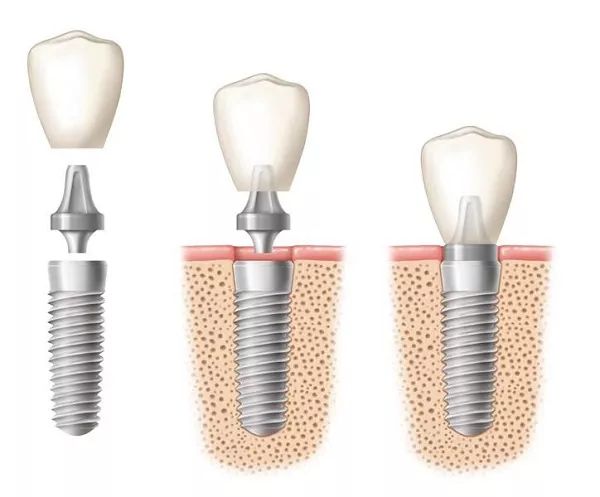

种植牙(Implant)就是将纯钛的人工牙根植入患者的颌骨内,以骨整合(Osseointegration)的方式与颌骨融合在一起,通过基台(Abutment)与上部的假牙(Crown)连接在一起而行使功能。

答:种植治疗一般可分为术前准备、种植体植入手术以及种植义齿修复三个阶段。

修复一般在手术后三-六个月进行。先要进行二期手术,再进行取模、义齿制作、戴牙等工作。治疗一般需要2-3周时间。